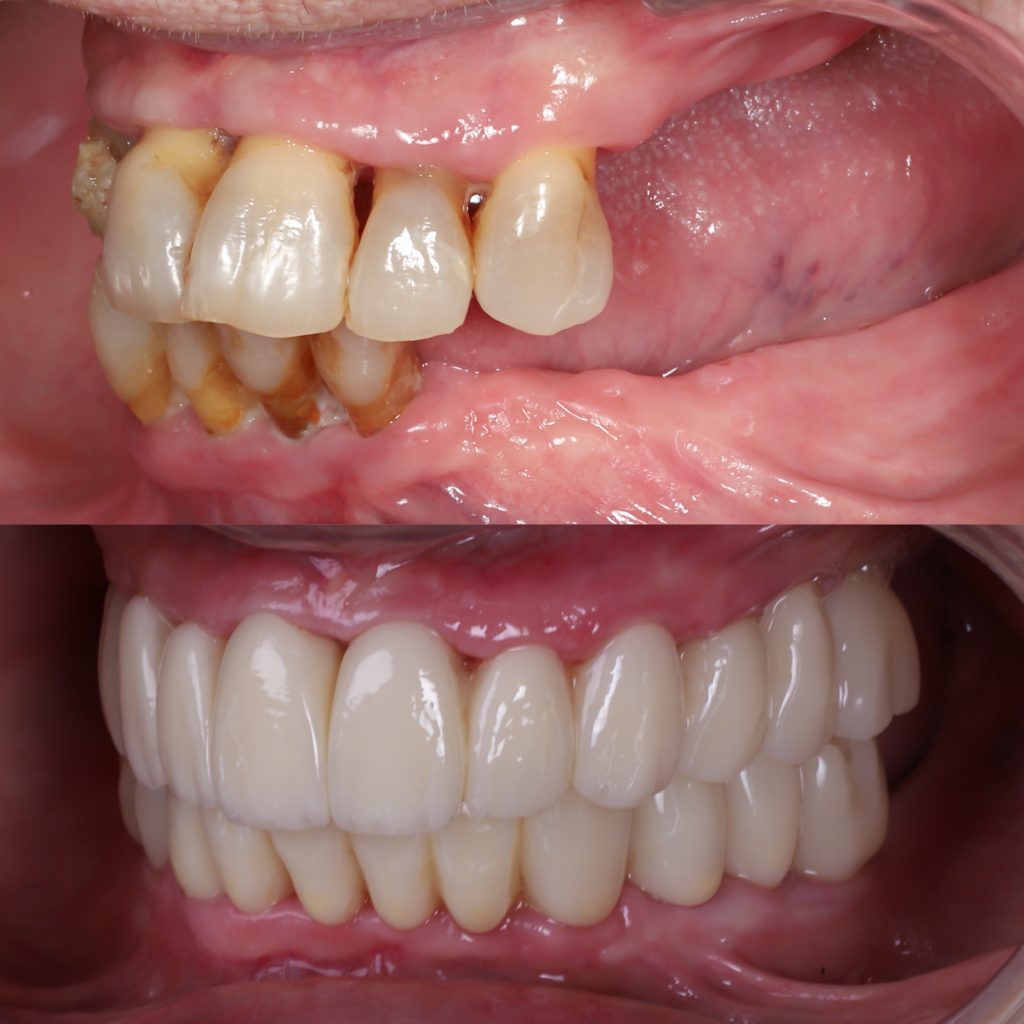

Este es un ejemplo de paciente con falta severa de hueso dental que solucionamos con implantes cigomáticos ya que era la solución ideal para este paciente.

- Implantes cigomáticos

Utilizan el hueso del pómulo cuando el maxilar superior está muy reabsorbido. - Implantes yuxtaóseos o subperiósticos

En muchos casos, la solución ideal no es una sola técnica, sino una combinación planificada: por ejemplo, regeneración ósea en ciertas zonas, implantes convencionales donde hay más hueso e implantes sin tornillos o cigomáticos en áreas con atrofia extrema. La Sociedad Española de Periodoncia y Osteointegracion recomienda la colocación de implantes dentales para evitar la pérdida de mayor masa ósea maxilar.